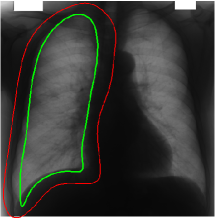

Refer to captionRefer to captionRefer to captionRefer to caption(a)(b)(c)(d)Refer to captionRefer to captionRefer to captionRefer to caption𝑎𝑏𝑐𝑑\begin{array}[]{cccc}\includegraphics[width=112.0187pt]{11-1-init.pdf}&\includegraphics[width=112.0187pt]{11-final.pdf}&\includegraphics[width=112.0187pt]{9-1-final.pdf}&\includegraphics[width=112.0187pt]{10-1-final.pdf}\\ (a)&(b)&(c)&(d)\end{array}

Figure 10: Segmentation of lungs using the mean template: (a) Initialization of template, (b) converged result. For the result shown in (c) and (d), an initialization similar to that shown in (a) was provided.

Yu et al. [35] reported good results for lung field and clavicle segmentation based on local differences of averages along the contour boundary. They start with an elliptical initialization and use dynamic programming to refine the contour. We also exploit the contrast between lungs and the rest of the body that X-ray imaging of the chest offers. We created a mean shape template from a set of training images using the methodology proposed in [36] and performed segmentation (refer Figure 10). The slight mismatch in shape between the mean template and the left lung in each image is evident from the results.